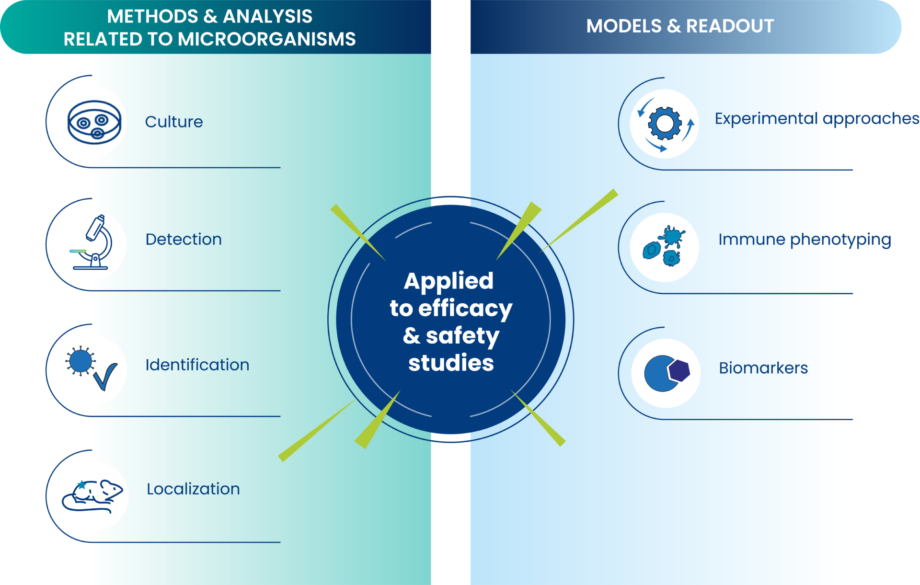

Models & Readouts in microbiome

Oncodesign Services proposes tools suitable for mimicking healthy and pathological situations, studying interplay with immune system for screening purpose and proof of concept.

- Experimental approaches

- In vitro 2D & 3D co-cultures

- SPF/SOPF, germ-free animals or with a custom microbiota

- Human biological specimen

- Immune phenotyping

- Cytokine profile

- Immune infiltrate

- Biomarkers

- Gut permeability (e.g. zonulin)

- Inflammation (e.g. calprotectin, lipocalin-2)

- Metabolites (e.g. short-chain fatty acids)

Methods & Analyses for microbiome studies

Oncodesign Services offers a broad range of technological approaches for culturing, detecting, identifying and localizing microorganisms (bacteria, yeasts, etc.) in simple or complex samples (fluids, tissues) coming from preclinical studies or clinical trials.

- Culture / Formulation

- Culture of aerobic or anaerobic bacteria and yeasts

- Preparation of single strain or consortium (with quality control of batches)

- Handling of wild type, engineered microbes or derivatives

- Formulation of frozen, lyophilized, pasteurized products

- Detection

- CFU counting

- qPCR coupled or not to PMA

- Identification

- Mass spectrometry

- qPCR/dPCR

- 16S rRNA gene sequencing

- Shotgun sequencing

- Phylopeptidomics

- Localization

- Imaging

- Ex vivo culture